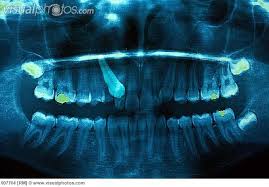

Learned About This Nope Today Hyperdontia Hyperdontia Dental Dental Fun